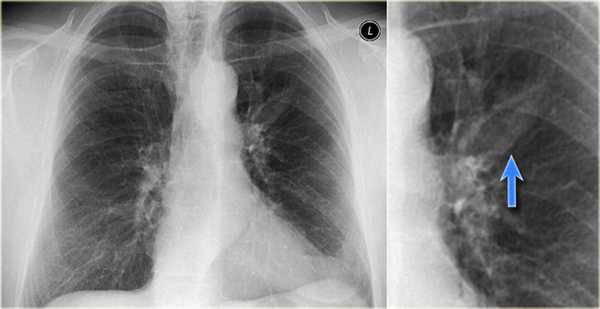

Бронхиальная атрезия

Бронхиальная атрезия — это врожденное заболевание бронхов, при котором визуализируется патологический бронх «забитый» слизью (красная стрелка) и гиперинфляция легкого (синяя стрелка).